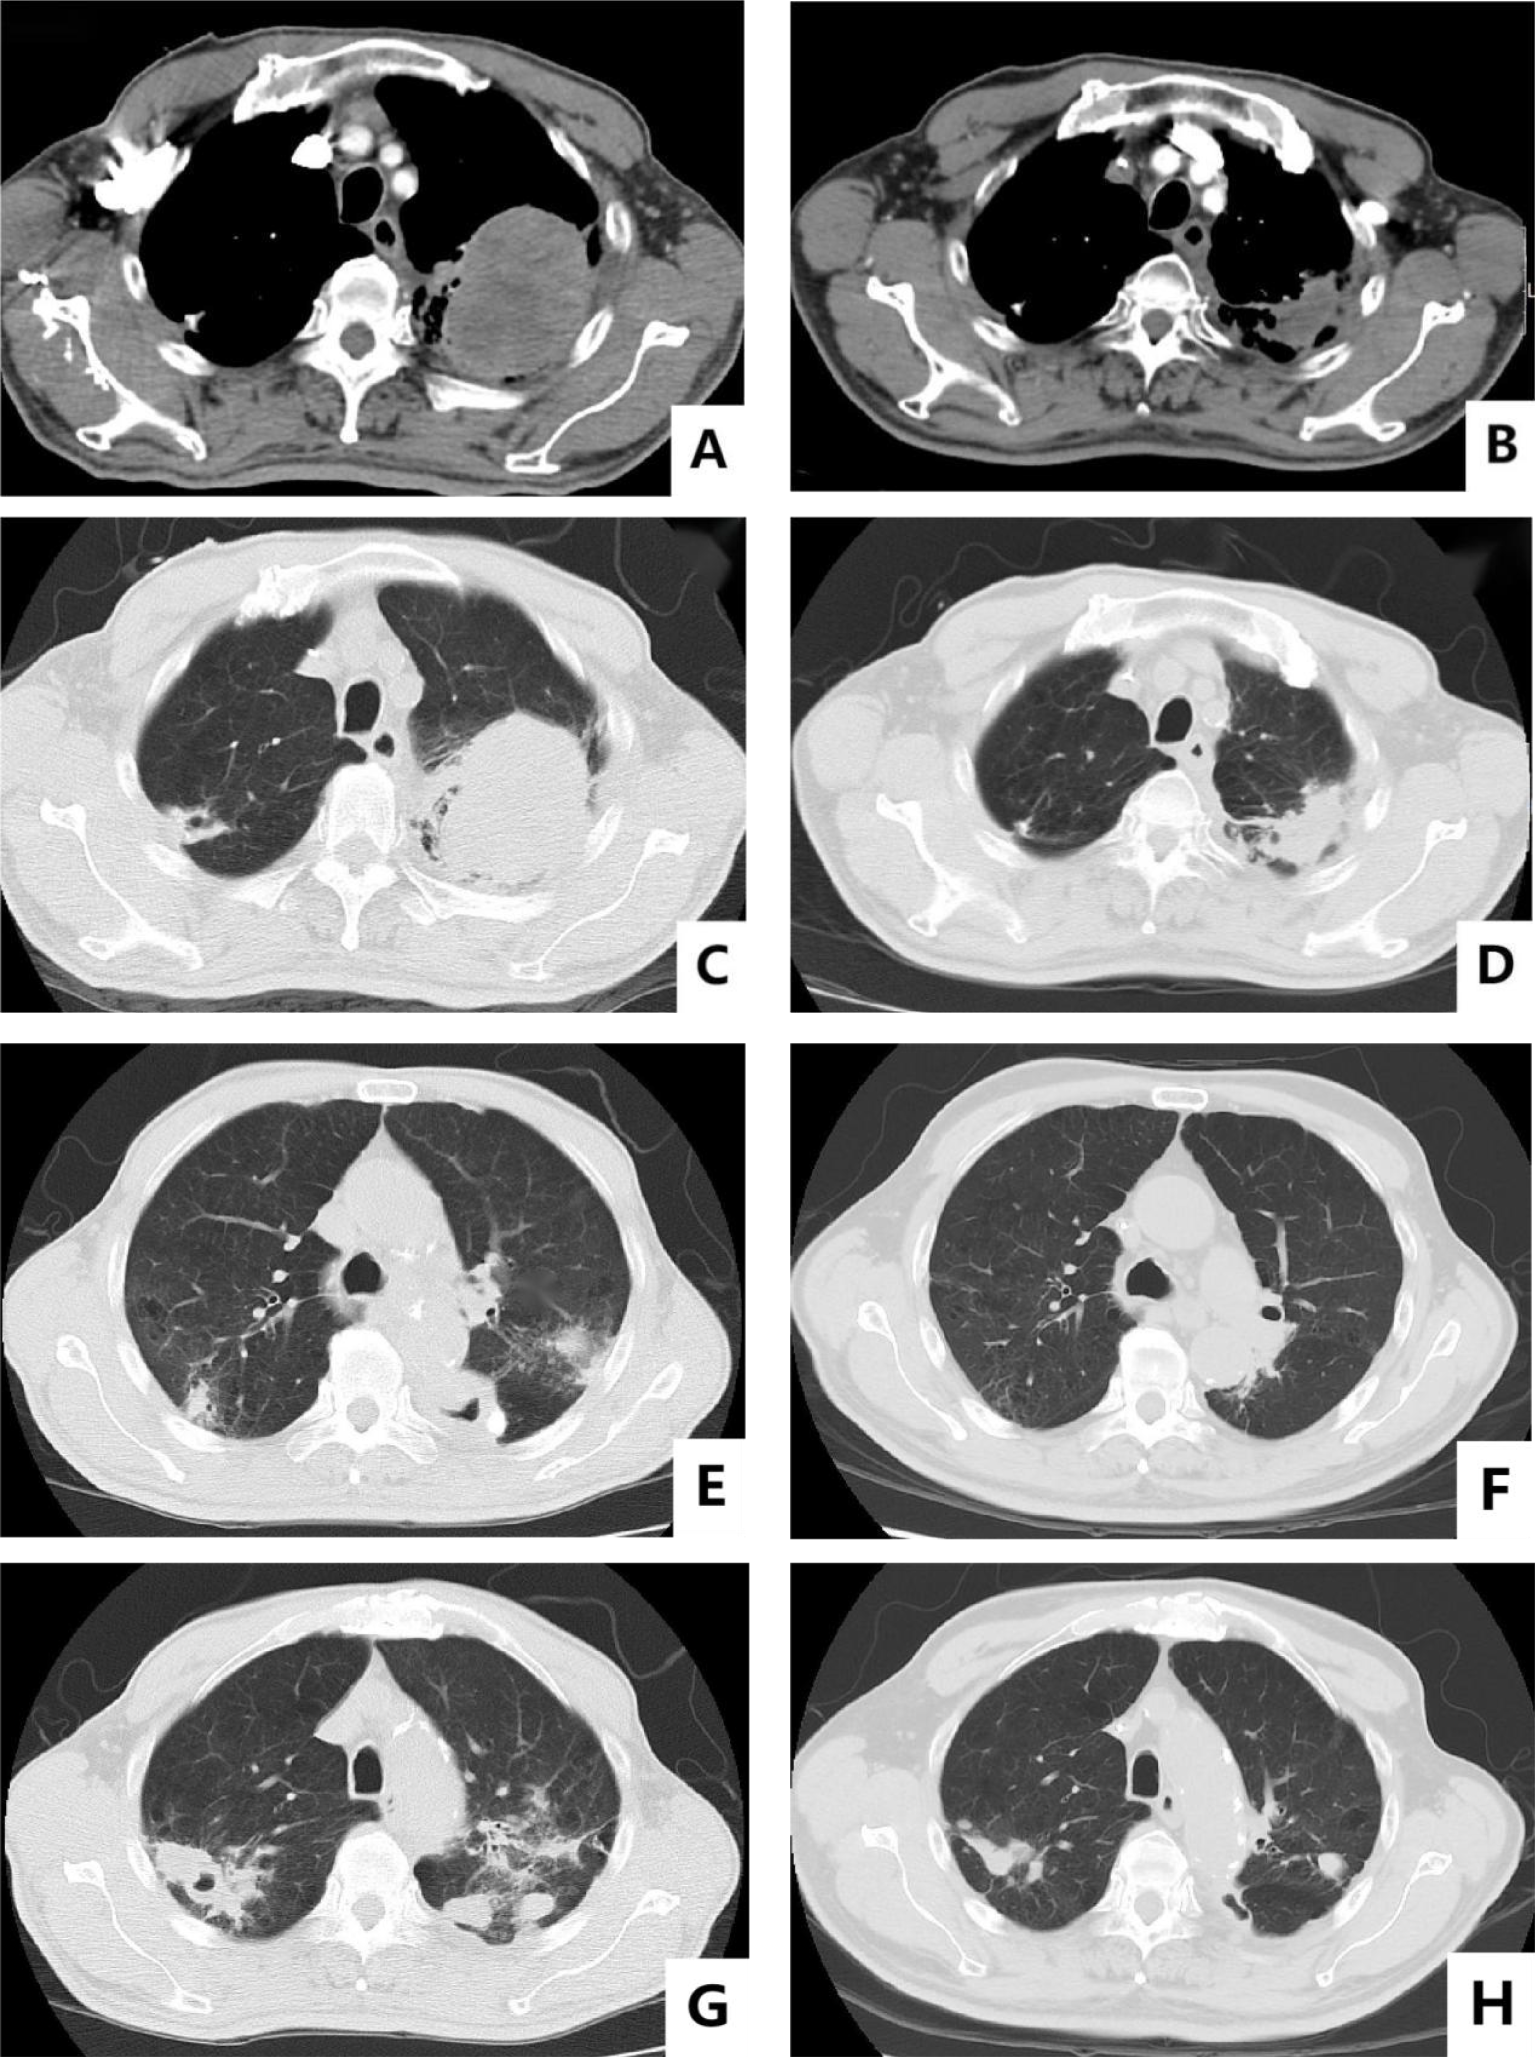

Figure 2

Baseline versus efficacy after four cycles of anti-tumor therapy: (A, C) show the images of baseline chest CT mediastinal window and lung window; (B, D) show the reexamination images after four cycles of anti-tumor therapy. Changes in pulmonary cavities after anti-TB treatment: (E, F) show the changes in the cavity in the left lung before and after treatment; (G, H) show the changes in the cavity in the upper right lung before and after treatment.